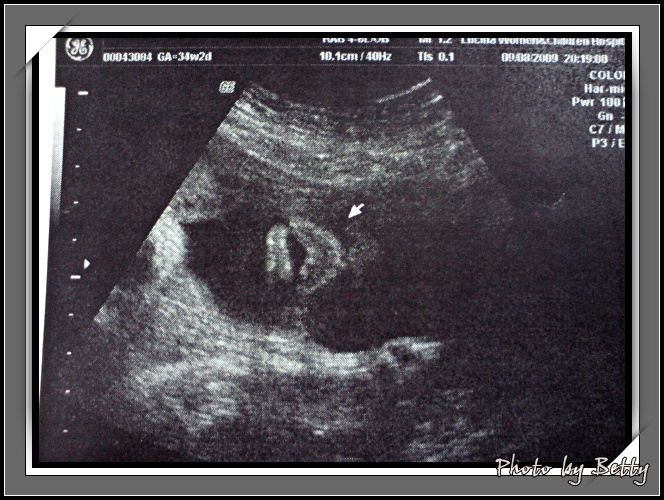

現在去作超音波越來越快,因為已經大到只能看到這種怪模樣 XD

這是小石頭的厚唇啦有沒有安潔莉娜的FU呢?